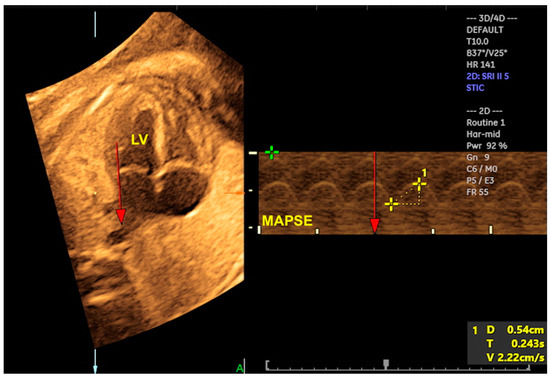

2.6. Cardiac Functional Evaluation

- Tedesco, G.D.; de Souza Bezerra, M.; Barros, F.S.; Martins, W.P.; Nardozza, L.M.; Carrilho, M.C.; Moron, A.F.; Carvalho, F.H.; Rolo, L.C.; Araujo Júnior, E. Reference Ranges of Fetal Cardiac Biometric Parameters Using Three-Dimensional Ultrasound with Spatiotemporal Image Correlation M Mode and Their Applicability in Congenital Heart Diseases. Pediatr. Cardiol. 2017, 38, 271–279. [Google Scholar] [CrossRef] [PubMed]

- Tanis, J.C.; Mohammed, N.; Bennasar, M.; Martinez, J.M.; Bijnens, B.; Crispi, F.; Gratacos, E. Online versus offline spatiotemporal image correlation (STIC) M-mode for the evaluation of cardiac longitudinal annular displacement in fetal growth restriction. J. Matern. Fetal Neonatal Med. 2018, 31, 1845–1850. [Google Scholar] [CrossRef]